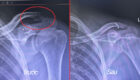

Trong vòng 1-2 ngày sau mổ, bệnh nhân sẽ được chụp X-quang hệ tiết niệu để kiểm tra tình trạng sót sỏi, kiểm tra xem sonde JJ có đúng vị trí không? Nếu đã sạch sỏi; sonde JJ đúng vị trí thì bệnh nhân có thể được rút ống dẫn lưu thận và ống tiểu. Ở vị trí dẫn lưu sau khi rút ống có thể xuất hiện tình trạng rỉ nước tiểu và sẽ chấm dứt sau 3 – 6 giờ nhờ băng ép. Nếu tình trạng này vẫn tiếp tục kéo dài cần báo ngay cho điều dưỡng.